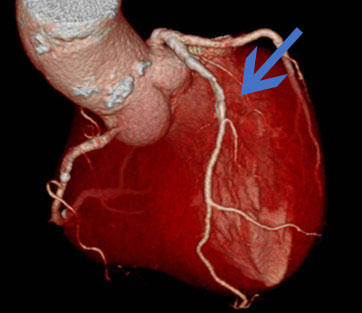

冠動脈CT検査

突然死の原因の1つである心筋梗塞のリスクとなる病変の早期発見に有効です。